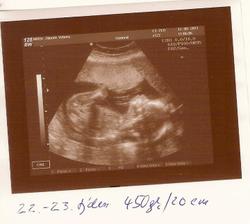

12.9.11 Emis je dle utz zcela zdrava, azi 440g, meri po prdelku 20cm, takze celkem cca 27cm, dalsi KO 10.10., predtim jeste absolvovat test na cukrovku.